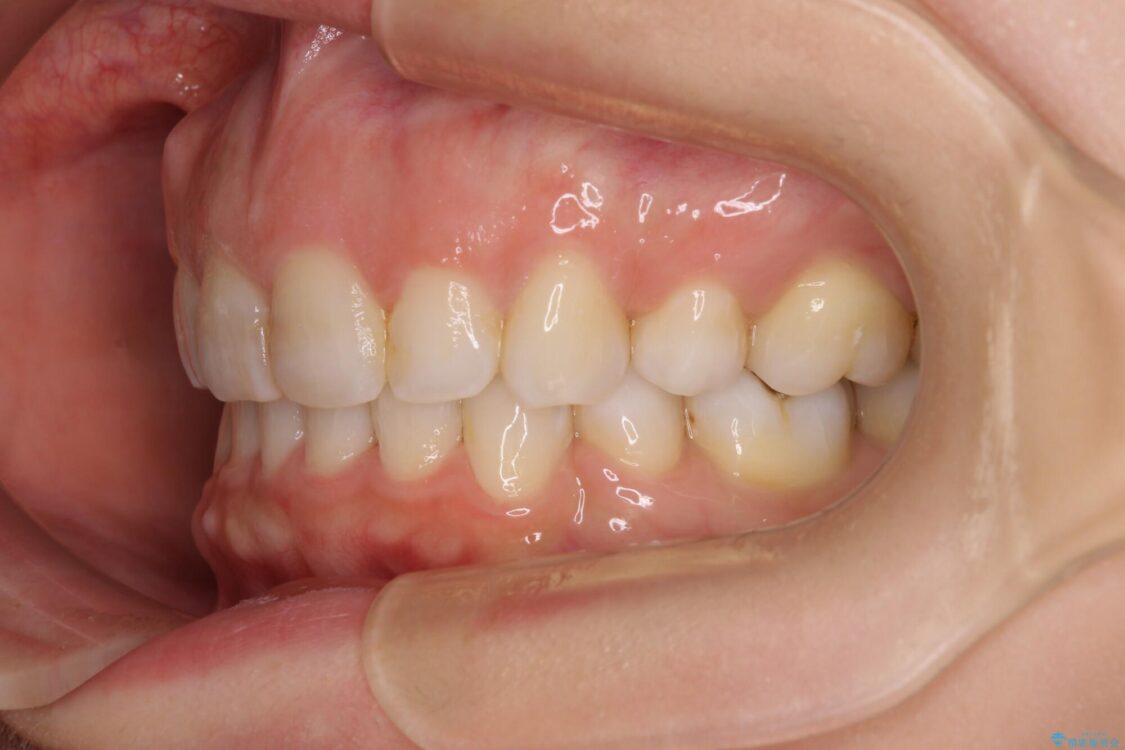

口元の閉じにくさと、奥歯の咬み合わせを気にして来院された患者様です。

左下の大臼歯2本が顕著に舌側に傾斜しているため、まずは奥歯の咬み合わせを改善をし、その後上下左右の第1小臼歯4本を抜歯することで口元を引っ込めながら整えることとしました。

治療前

• 【モニター】出っ歯と咬み合わせを改善 ワイヤー装置の抜歯矯正 治療前画像